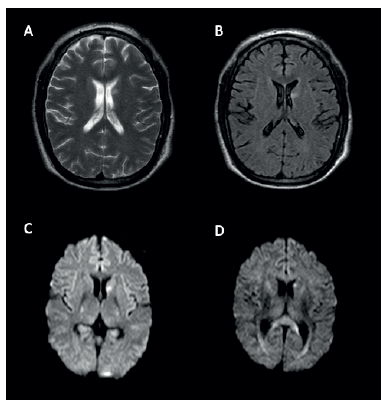

<p>A la evaluación física se observaron mioclonías tanto positivas como negativas e hiperreflexia generalizada, el resto del examen neurológico fue normal. Se identificaron factores promioclónicos como medicamentos que el paciente estaba recibiendo; ante la sospecha de mioclonías de origen cortical o espinal se solicitó resonancia magnética contrastada cerebral y de columna cervical. La resonancia de cerebro mostró un evento isquémico subagudo en núcleo caudado izquierdo, y se muestra en la <xref ref-type="fig" rid="f1">figura 1</xref>. Adicionalmente, un estudio electroencefalográfico descartó actividad epileptiforme.</p>

<attrib>Nota: Secuenc¡a de cortes ax¡ales: A. T2; B. FLAIR; C. ¡soB1000; D. Imagen ponderada en d¡fus¡ón (DWI), compatibles con evento ¡squém¡co subagudo en terr¡tor¡o de núcleo caudado ¡zqu¡erdo.</attrib>